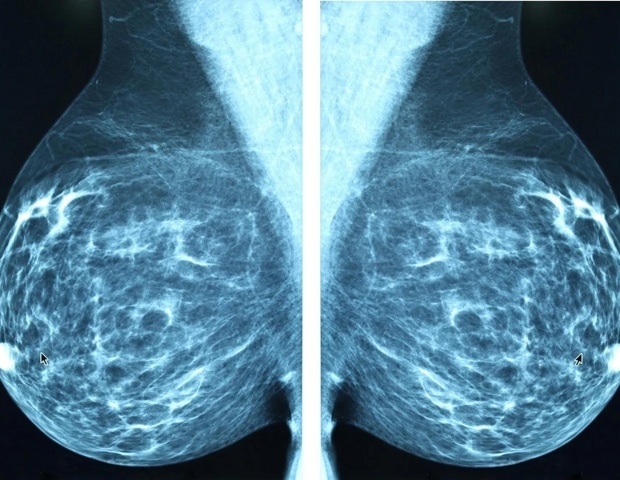

Μια νέα μελέτη που δημοσιεύθηκε στο Clinical Cancer Research από επιστήμονες του UPMC Hillman Cancer Center και της Ιατρικής Σχολής του Πανεπιστημίου του Πίτσμπουργκ, υποδεικνύει ότι μια δοκιμή αίματος μπορεί να προσφέρει πολύτιμες πληροφορίες για τη θεραπεία μιας προσεκτικά επιλεγμένης ομάδας γυναικών άνω των 70 ετών που έχουν καρκίνο του μαστού θετικό στους υποδοχείς οιστρογόνων. Αυτές οι γυναίκες εξετάζουν την ορμονική θεραπεία ως κύρια θεραπεία, αποφεύγοντας τη χειρουργική επέμβαση και την ακτινοθεραπεία.

Οι ερευνητές ανέλυσαν δείγματα αίματος για κυκλοφορούν DNA όγκου (ctDNA), μικρά κομμάτια γενετικού υλικού που απελευθερώνονται από τα καρκινικά κύτταρα. Εξέτασαν αν η παρουσία ή η απουσία αυτών των θραυσμάτων θα μπορούσε να προσδιορίσει ποιες ασθενείς δεν θα ανταποκριθούν στην ορμονική θεραπεία.